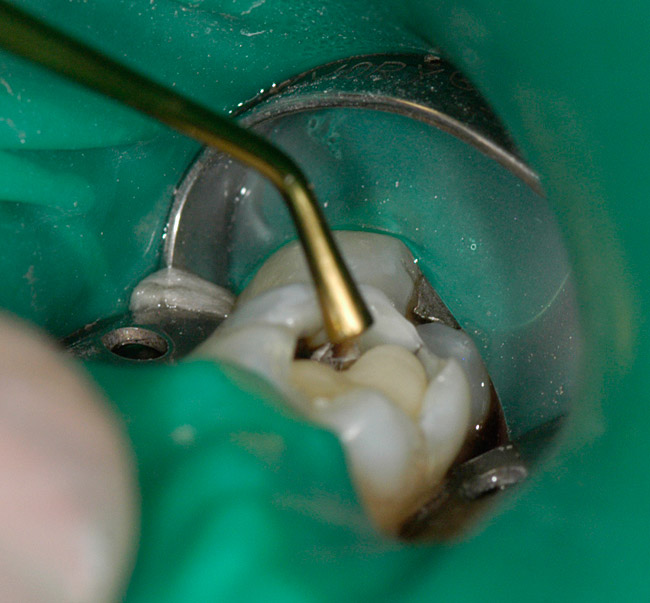

Figure 3  After the flowable base has set, the cavity preparation is etched for 15 seconds and thoroughly rinsed with water and blotted dry.

Figure 3